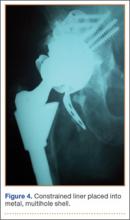

Although the number of total hip arthroplasties (THAs) being performed in the United States is increasing, revision THAs are more common.1 Many acetabular revisions can be successfully performed with standard or jumbo cementless acetabular cups, but major osseous deficiencies typically require reconstruction with a cage or cup/cage that bridges gaps in the pelvis and obtains fixation of the arthroplasty components.2,3 Cages and rings have been combined with all-polyethylene acetabular components (ie, all-polyethylene cups, or APCs) to reconstruct pelvic bone defects, but complications, including APC dissociation (Figure 1) and postoperative instability, can occur despite stable fixation of cage to pelvis.4 The incidence of dislocations with pelvic reconstruction rings using APCs has been reported to be 11%.4 If an APC has to be replaced because of wear, then major surgery may be required to extract the worn cup and cement a new cup in its place.